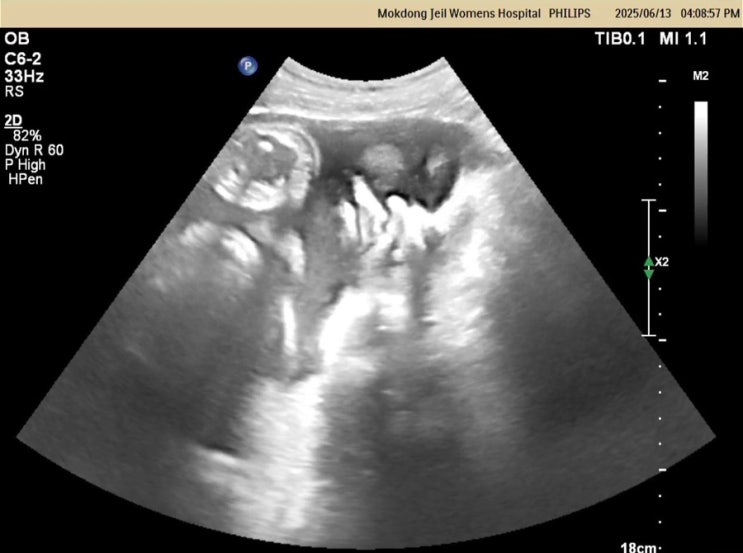

2025.06.18(출산 예정일) 드디어 출산 예정일이 되었다. 오늘도 전혀 소식이 없는 젤로 병원에 방문해서 태...